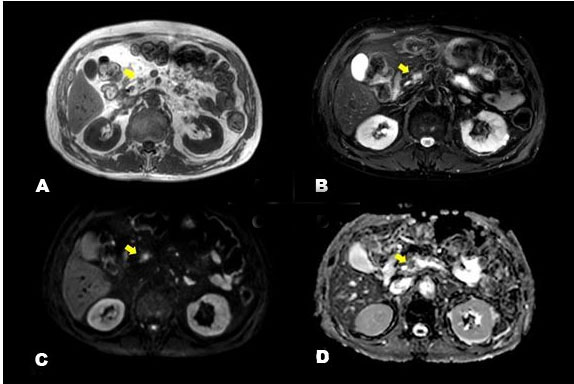

We conducted 3-T contrast-enhanced MRI which revealed a low-intensity mass of approximately 1 cm in the pancreatic head on T1-weighted images and on T2 fat suppression; it was recognized as a tumor, exhibiting clearer high-intensity than did the adipose tissue (Figure 5). In addition, the lesion showed high intensity on diffusion-weighted imaging (DWI) and low intensity on the apparent diffusion coefficient (ADC), indicating that pancreatic cancer was present in the pancreatic head. Gadolinium-enhanced MRI (Figure 6) revealed that the mass was late-enhanced, and we were able to make a definitive diagnosis of pancreatic cancer. Endoscopic retrograde pancreatography (ERP) and magnetic resonance cholangiopancreatography (MRCP) (Figure 7) confirmed disruption of the main pancreatic duct and dilation of the pancreatic duct. Serial pancreatic juice aspiration cytological examination (SPACE) was performed. After performing endoscopic nasopancreatic drainage and pancreatic duct brush cytology, pancreatic juice was collected thrice via a pancreatic catheter. Cytopathology revealed class IIIa disease (Papanicolaou classification). Based on the imaging test results, the patient was confidently diagnosed with pancreatic cancer (T1c, N0, M0, stage IA), and we decided to perform pancreaticoduodenectomy as treatment.

Figure 5: Images from 3-T enhanced magnetic resonance imaging (MRI) are shown. The T1-weighted image (in-phase) (A), T2-weighted image (fat suppression) (B), diffusion-weighted image (DWI) (C), and the apparent diffusion coefficient (ADC) (D) are shown. All yellow arrows point to the tumor. On the T1-weighted image, a low-intensity mass of approximately 1 cm was observed in the pancreatic head, and on the fat-suppressed T2-weighted image, it was recognized as a tumor, exhibiting clearer high-intensity than the adipose tissue. The DWI shows a high signal, and the ADC shows a low signal.